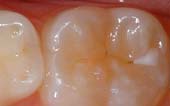

Seal Out Decay

A sealant is a protective coating that is applied to the chewing surfaces (grooves) of the back teeth (premolars and molars), where four out of five cavities in children are found. This sealant acts as a barrier to food, plaque and acid, thus protecting the decay-prone areas of the teeth.